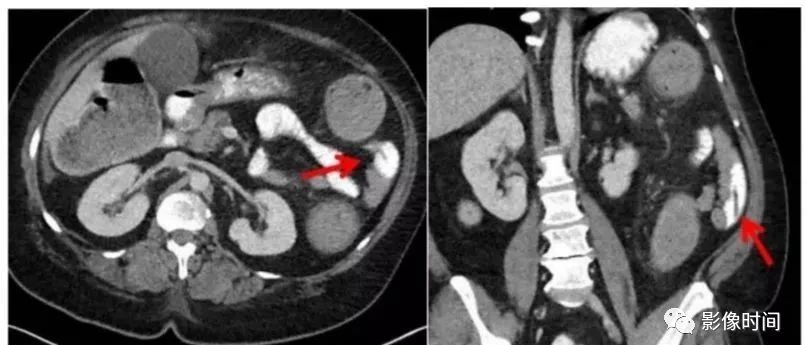

一文秒懂蛔虫病的CT诊断